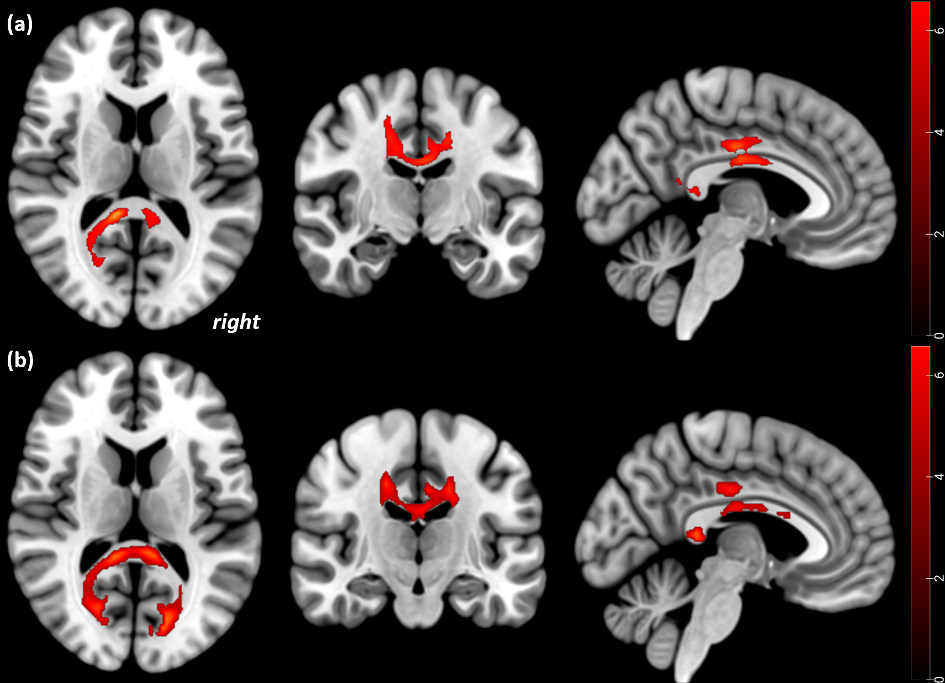

Attachment trauma becomes apparent in region-specific white matter alterations in adolescent patients with Anorexia Nervosa before and after treatment

Fig. 1:Statistical parametric mapping (t) intensity projection maps rendered onto a stereotactically normalized MRI scan, voxel cluster of the significant FA alterations in AN (statistical significance is thresholded at p < 0.001, FWE p < 0.05 corrected at the cluster level). FA decreases in acute AN patients with attachment trauma relative to HC at Tp1 (a), and at Tp2 (b). The right side of the image corresponds to the right side of the brain (Gander et al., 2023)

- Gander, M., Lenhart, L., Steiger, R., Buchheim, A., Mangesius, S., Birkl, C., Haid-Stecher, N., Fuchs, M., Libal, A., Dabkowska-Mika, A., Gizewski, R. & Sevecke, K. (2023). Attachment trauma is associated with white matter fiber microstructural alterations in adolescents with Anorexia Nervosa before and after exposure to psychotherapeutic and nutritional treatment. Brain Sciences, 13 (5), 7. doi: 10.3390/brainsci13050798